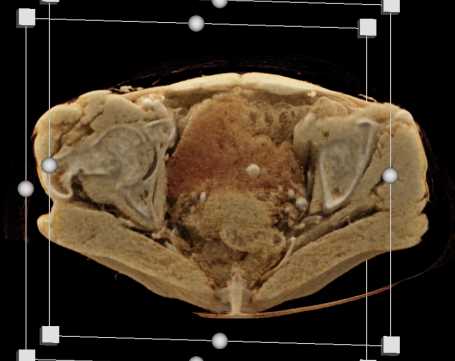

Urachal Carcinoma of the Bladder